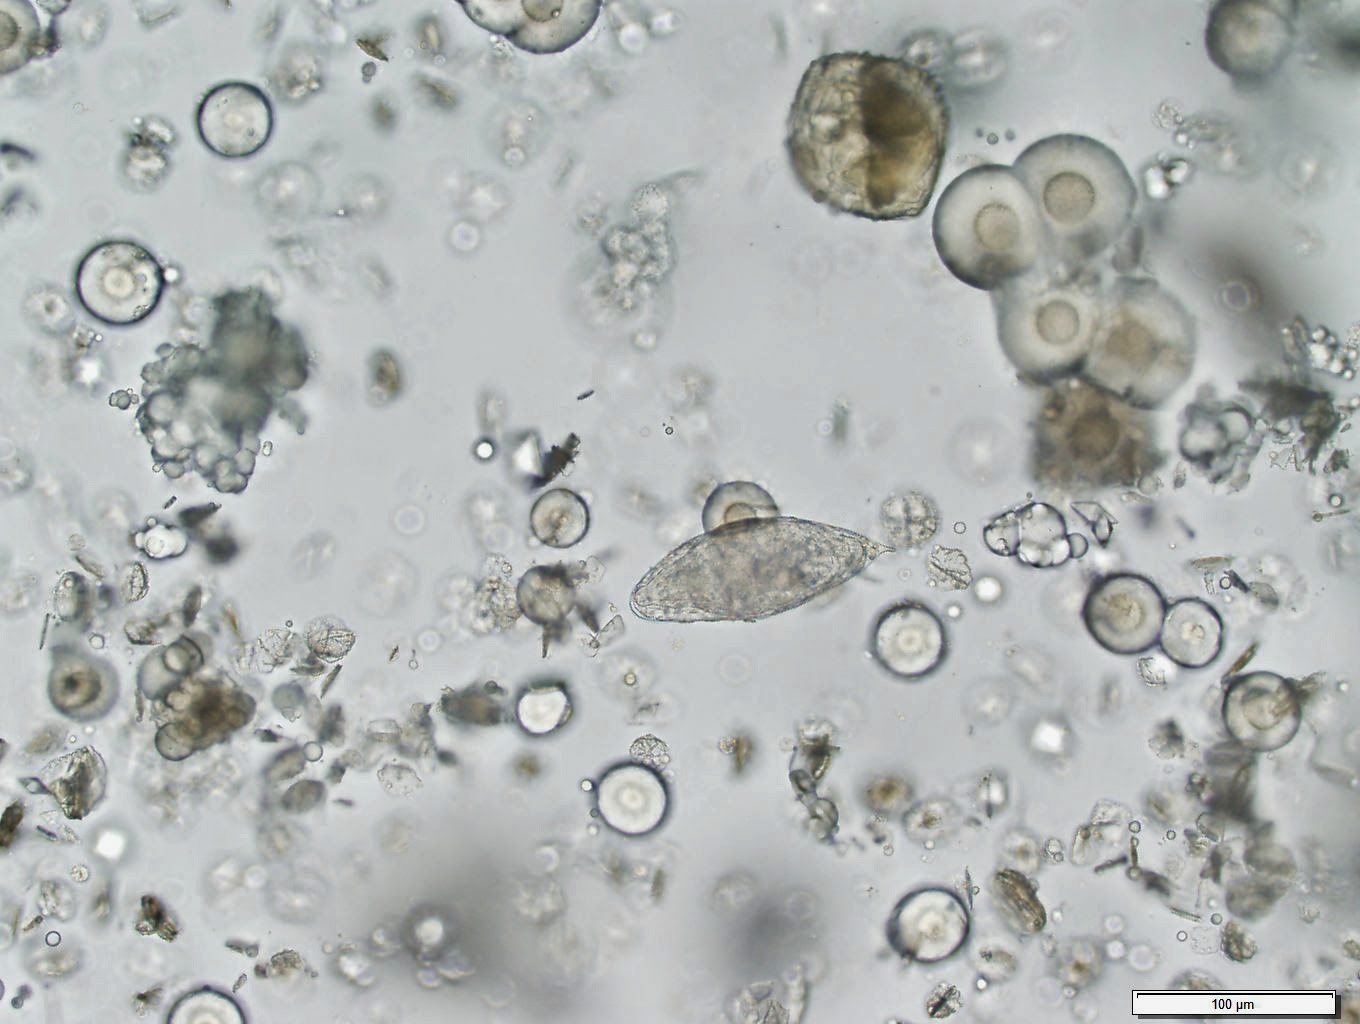

Giardia infection is caused by a. Providers diagnose parasitic infections by looking for parasites or signs of parasites (like their eggs) in body fluids or tissues. A tapeworm is a parasite that can live and feed in human intestines.

If you have diarrhea, drink a lot of fluids while sick to avoid dehydration (loss of fluids). The only way to diagnose intestinal worm parasites is by seeing eggs, larvae, or adult worms in the stool or, in the case of pinworm, collecting eggs from. Roundworms can live in the human intestine for a long time.

Giardia infection is an intestinal infection marked by stomach cramps, bloating, nausea and bouts of watery diarrhea. By looking at a blood smear under a microscope, parasitic diseases such as filariasis, malaria, or babesiosis, can be diagnosed.this test is done by placing a drop of blood. How do i know if i have parasites?

The stool o&p test is a common way to find out if you have parasites in your digestive tract. Some people may not have any symptoms from infection. Infants and pregnant women may be more likely to become dehydrated from.